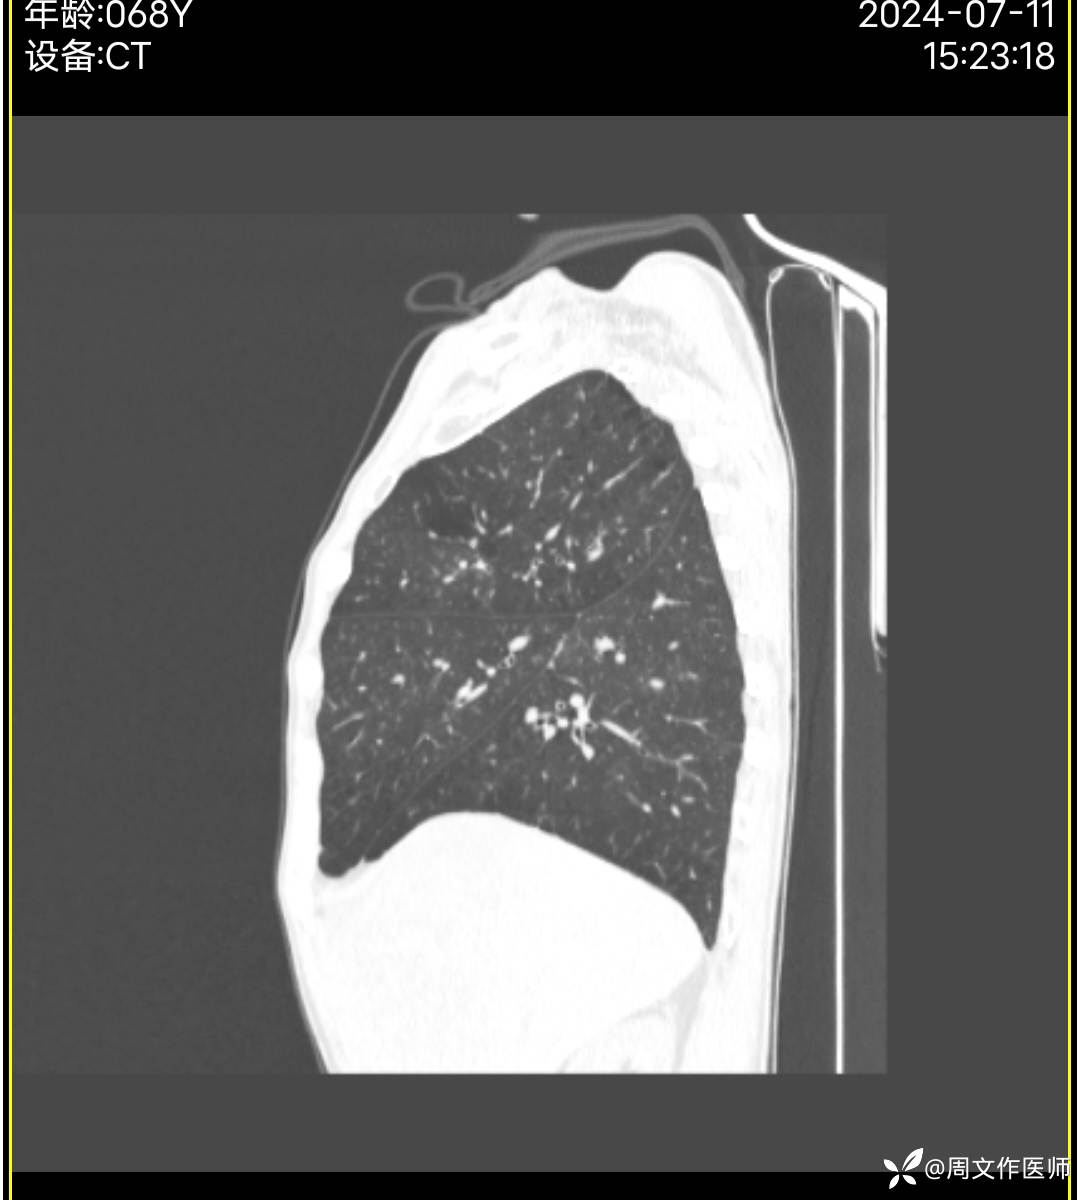

胸部CT检查